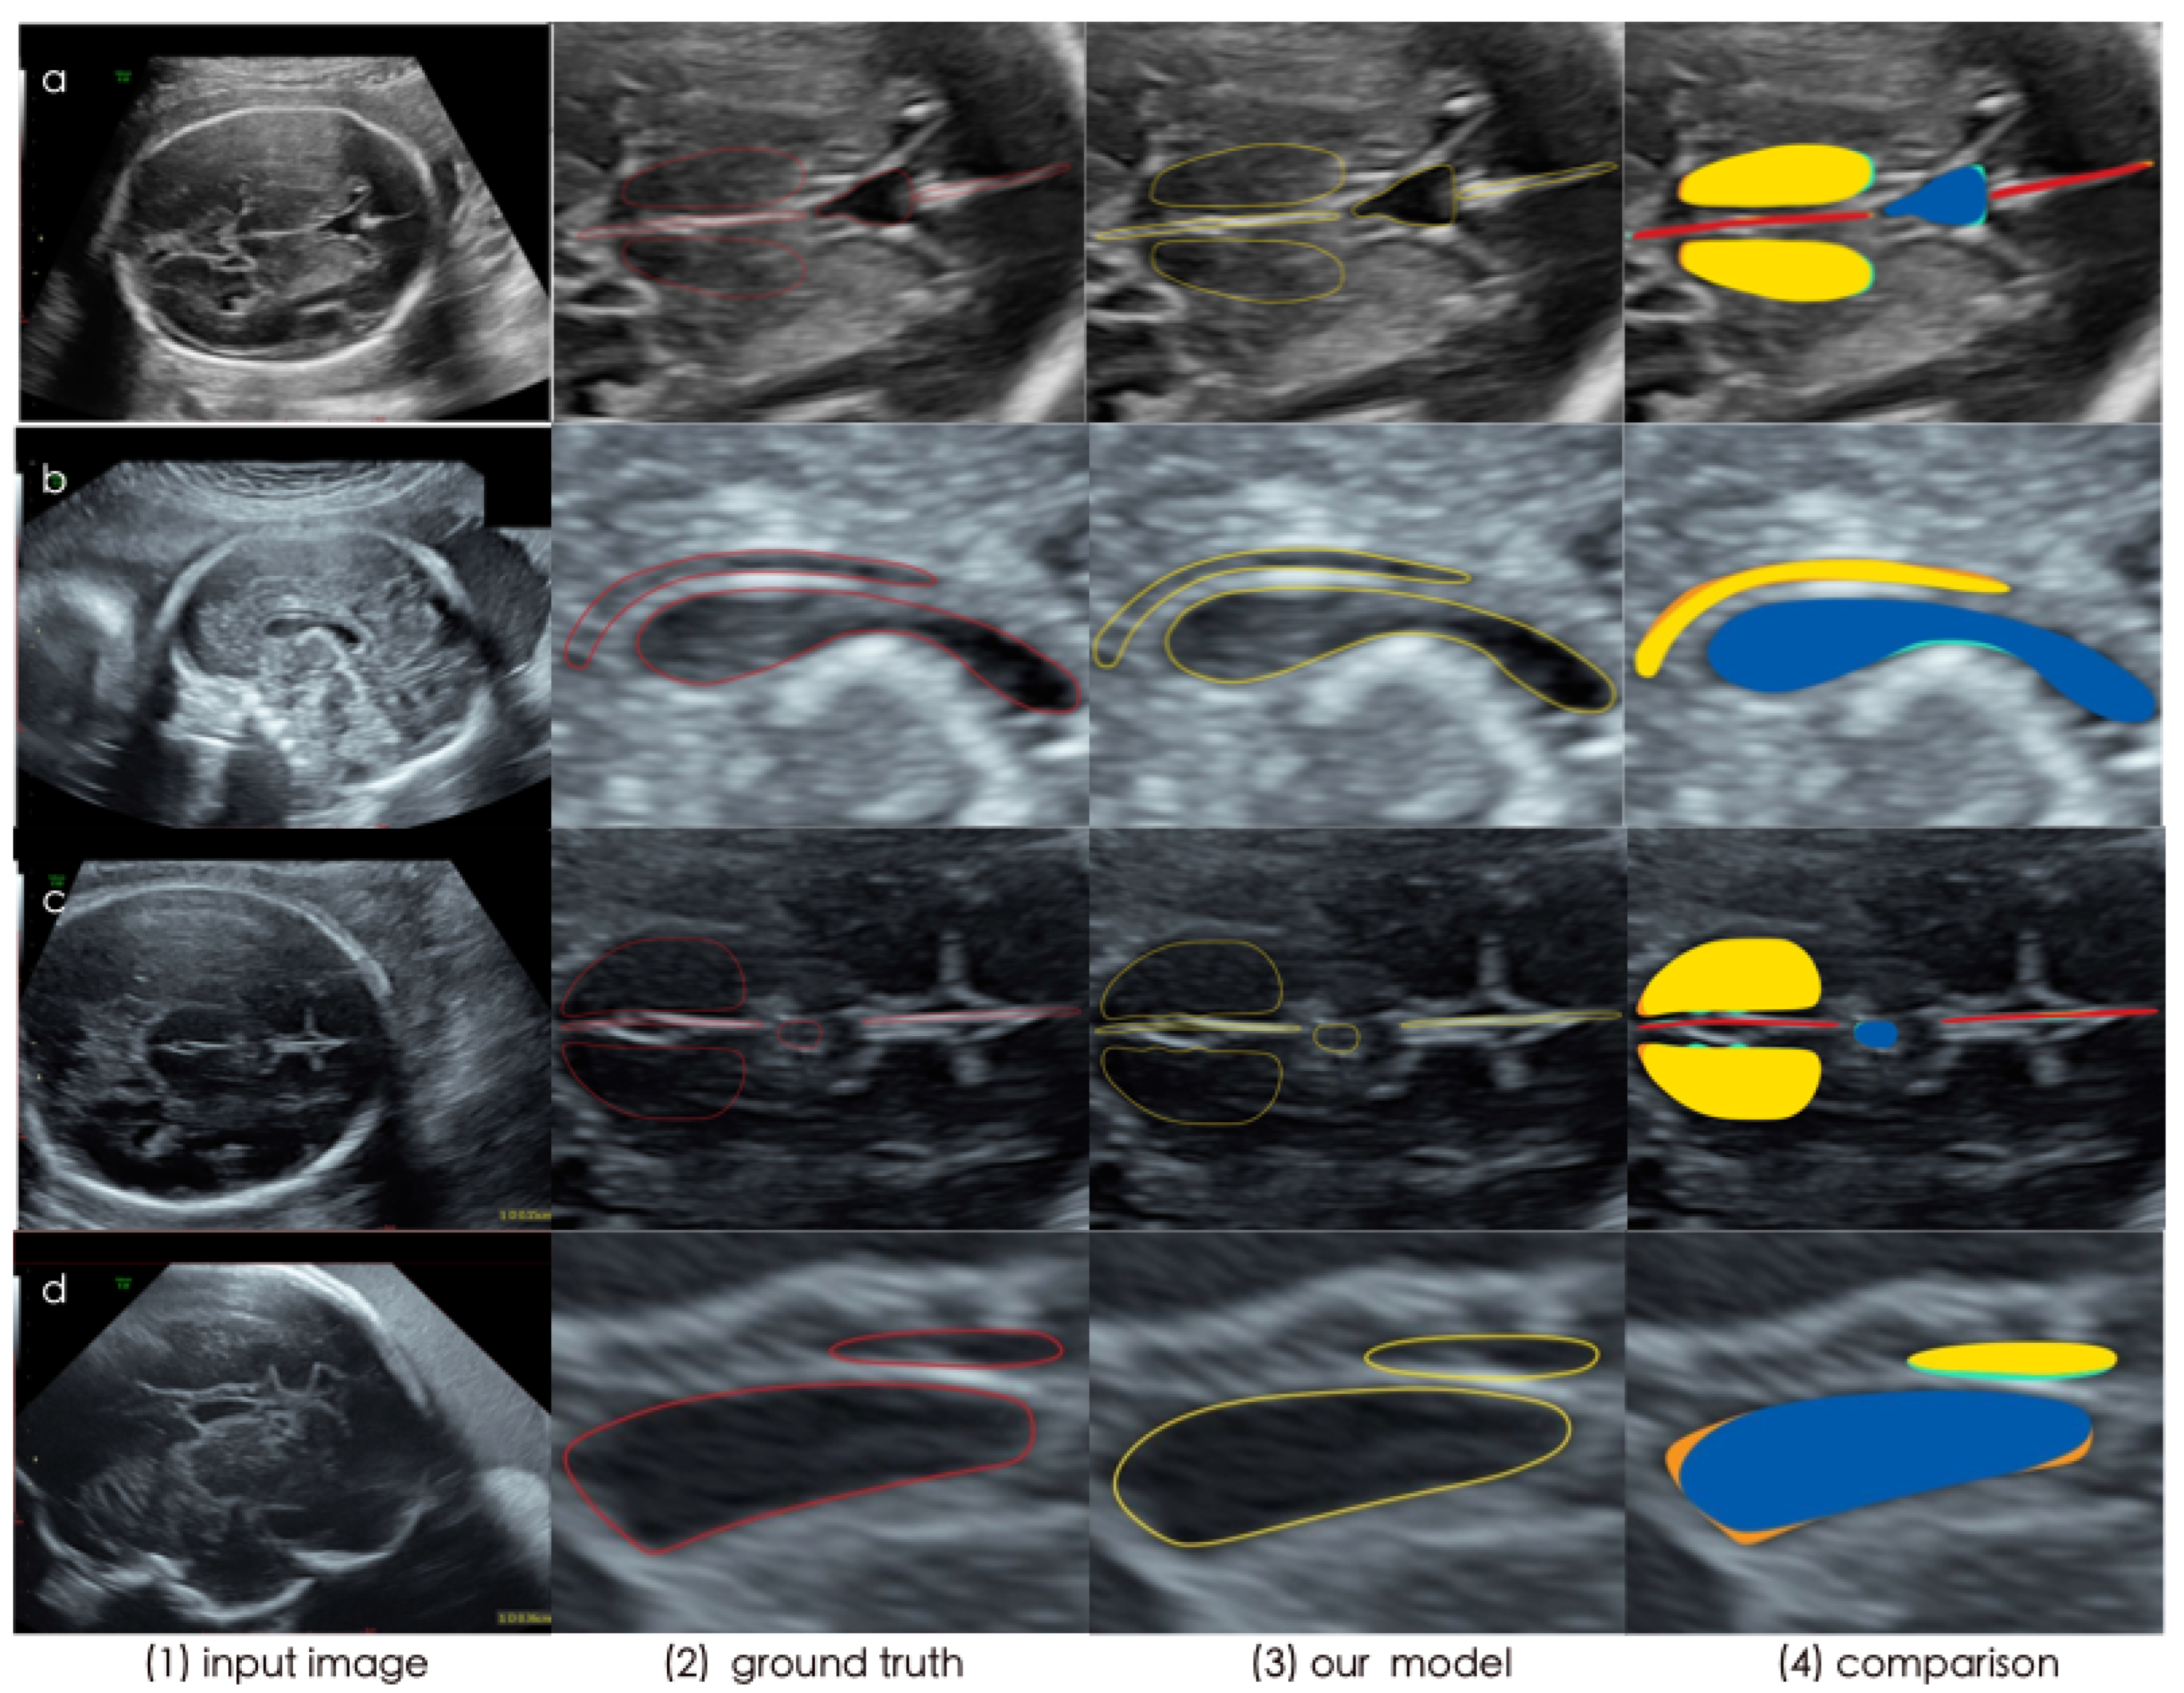

- Our data-driven system considers the measurement process of clinicians to tackle the automated problem of fetal biometrics measurement. Post-processing is proposed to measure and diagnose the anomalies of CSP. For validation, we have collected fetal US datasets in Xiangya hospital, on which our method achieves a Dice score (DSC) of 77.5% and precision of 79.5%. Our CA-Unet achieves the best segmentation performance among other state-of-art models, Experimental results demonstrate that it could effectively enhance obstetricians’ working efficiency and reduce their misdiagnosis rate.